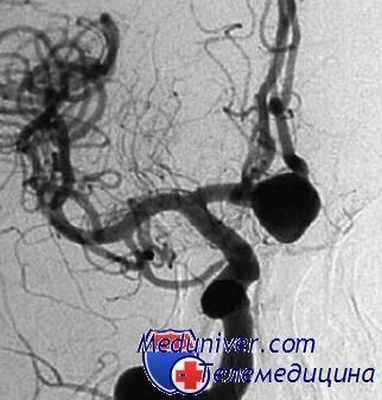

На следующий день (5-е сутки после САК) после стабилизации состояния пациентке была проведена операция — эндоваскулярная окклюзия аневризмы в области развилки правой ВСА микроспиралями (рис. 2).

Рисунок 2. Каротидная ангиограмма до операции (а). Аневризма развилки ВСА заднего расположения (указана стрелкой). Ангиографмма после окклюзии аневризмы микроспиралями (б). Больная перенесла операцию удовлетворительно, при ангиографии отмечено умеренное сужение артерий.